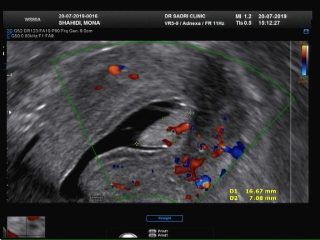

در این مورد ممکن است سونوگرافی کالر داپلر به صورت تکمیلی انجام شود. در تصویر زیر نمونه ای از پولیپ را مشاهده می کنید که توسط کالر داپلر عروق مرکزی تغذیه کننده نشان داده شده است:

عکس مربوط به سونو هیسترو است و در قسمت بالای کاویته رحمی تصویر یک پولیپ با پدیکل عروقی آن که از لایه قدامی اندومتر منشا گرفته رویت میشود: